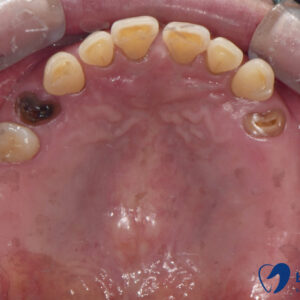

실제로 저희 치과 환자분의 인상 채득 과정 중

트리오스 5를 사용하여 구강 스캔을 진행 한 모습입니다.

진료 중 스캔 된 이미지는 스캔 즉시 바로 컴퓨터에 저장되어 3D로 확인이 가능하며

여러 각도에서 치아의 형태, 위치, 간격 등을 볼 수 있을 뿐만 아니라

완성될 보철의 형태 또한 예측할 수 있습니다.